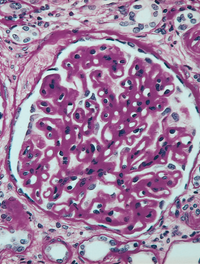

La glomérulonéphrite extra-membraneuse (GEM) est la principale cause de syndrome néphrotique chez l’adulte. Elle est le plus souvent [...]

La néphropathie à IgA, décrite il y une cinquantaine d’années, est la plus fréquente des glomérulonéphrites chroniques à l’échelon [...]